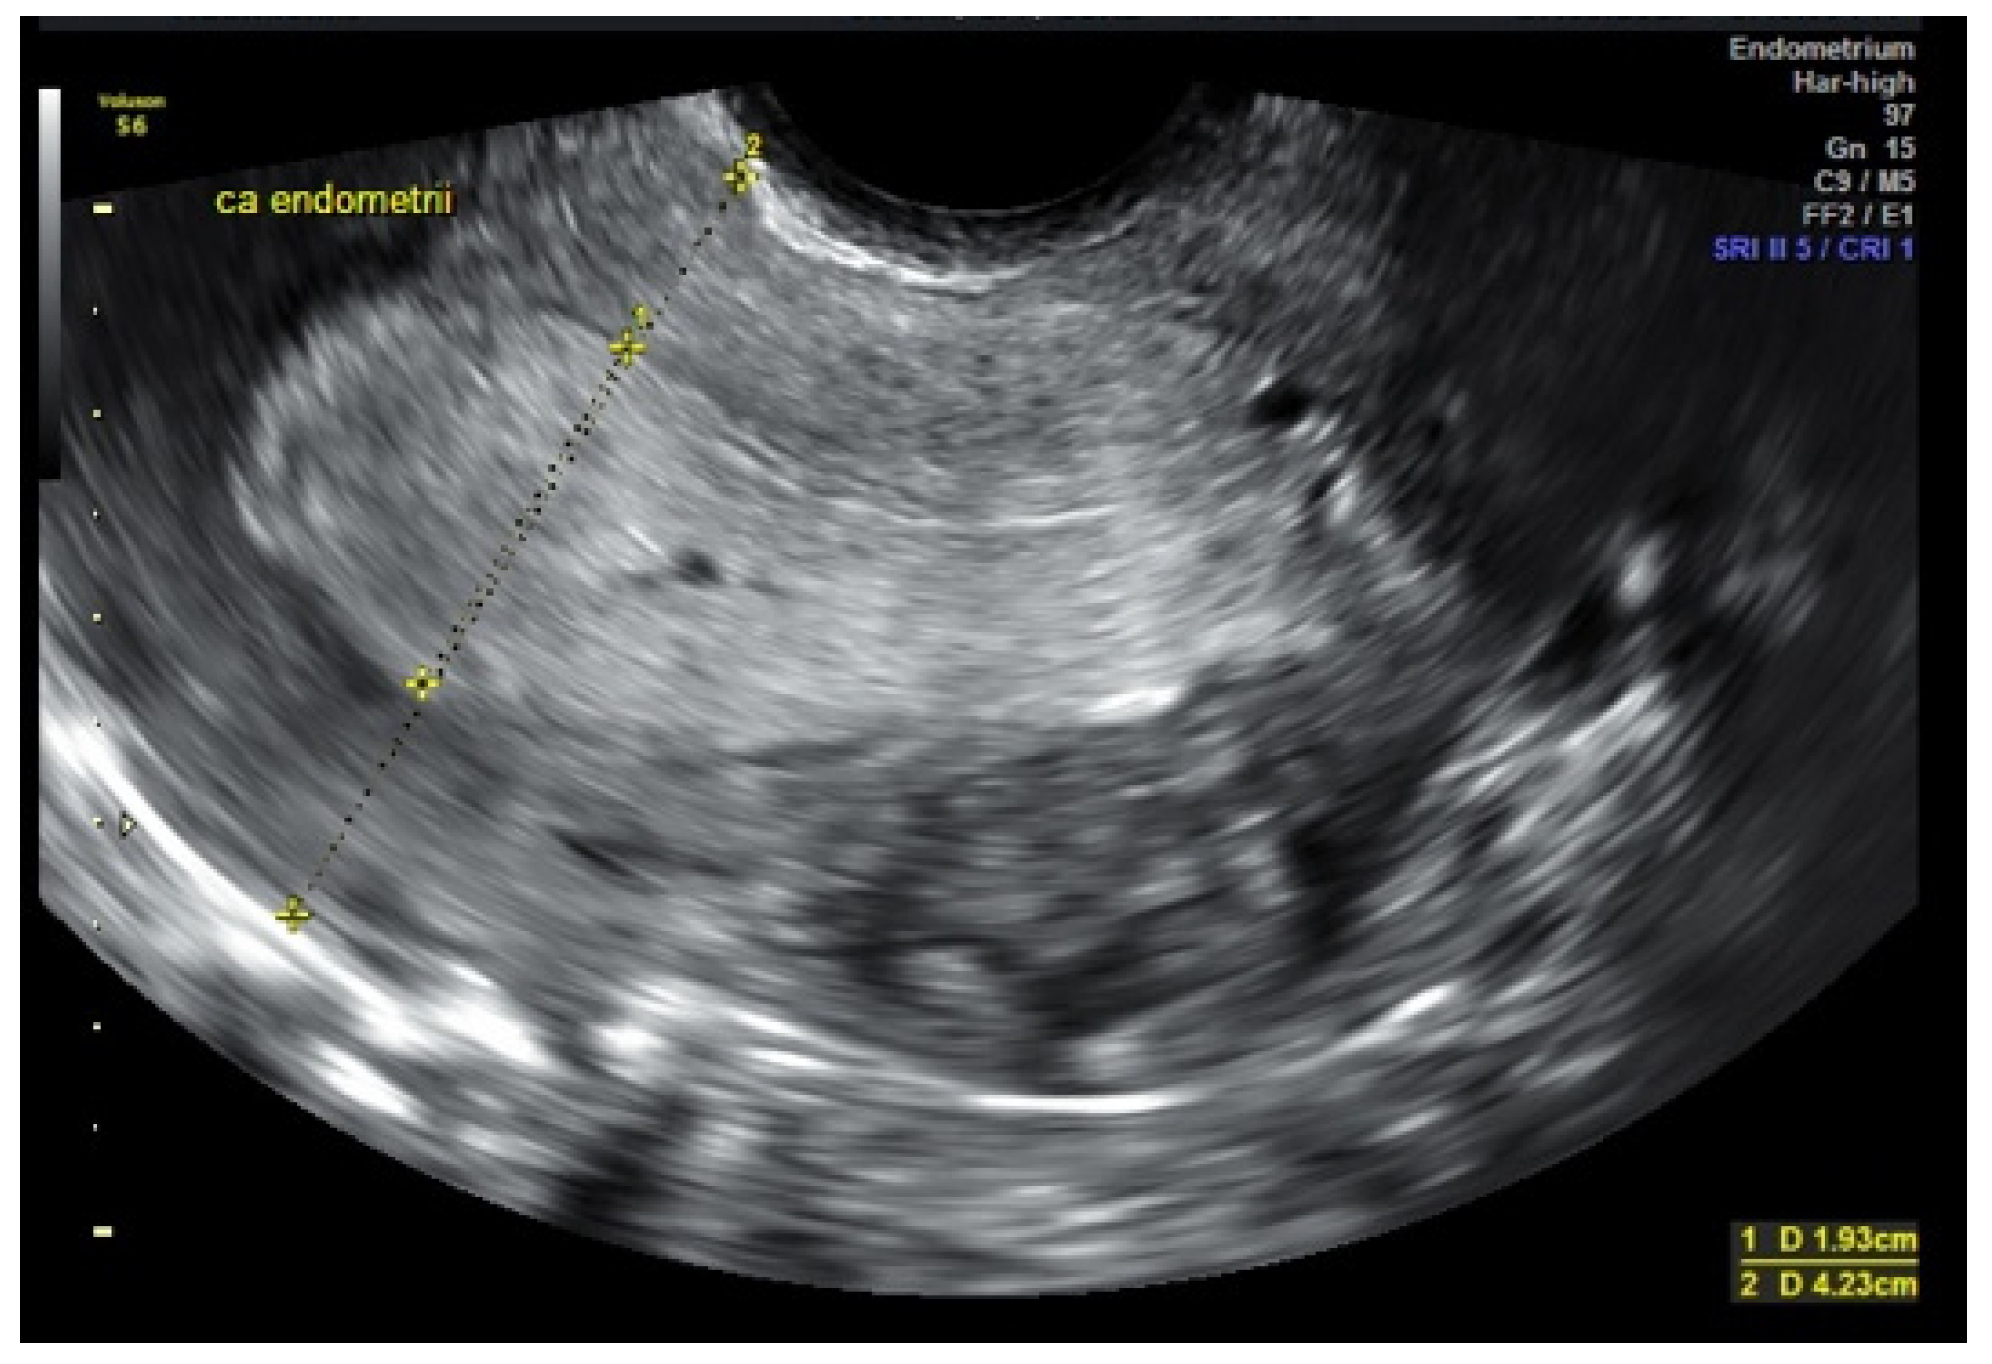

3.1. USG (Ultrasonography) and MRI (Magnetic Resonance Imaging)

- Eriksson, L.S.; Lindqvist, P.G.; Rådestad, A.F.; Dueholm, M.; Fischerova, D.; Franchi, D.; Jokubkiene, L.; Leone, F.P.; Savelli, L.; Sladkevicius, P.; et al. Transvaginal ultrasound assessment of myometrial and cervical stroma invasion in women with endometrial cancer: Interobserver reproducibility among ultrasound experts and gynaecologists. Ultrasound Obstet. Gynecol. 2015, 45, 476–482. [Google Scholar] [CrossRef]

- Capozzi, V.A.; Rosati, A.; Rumolo, V.; Ferrari, F.; Gullo, G.; Karaman, E.; Karaaslan, O.; HacioĞlu, L. Novelties of ultrasound imaging for endometrial cancer preoperative workup. Minerva Med. 2021, 112, 3–11. [Google Scholar] [CrossRef] [PubMed]

- Savelli, L.; Ceccarini, M.; Ludovisi, M.; Fruscella, E.; De Iaco, P.A.; Salizzoni, E.; Mabrouk, M.; Manfredi, R.; Testa, A.C.; Ferrandina, G. Preoperative local staging of endometrial cancer: Transvaginal sonography vs. magnetic resonance imaging. Ultrasound Obstet. Gynecol. 2008, 31, 560–566. [Google Scholar] [CrossRef]

- Alcázar, J.L.; Orozco, R.; Martinez-Astorquiza Corral, T.; Juez, L.; Utrilla-Layna, J.; Mínguez, J.A.; Jurado, M. Transvaginal ultrasound for preoperative assessment of myometrial invasion in patients with endometrial cancer: A systematic review and meta-analysis. Ultrasound Obstet. Gynecol. 2015, 46, 405–413. [Google Scholar] [CrossRef] [PubMed]

- Epstein, E.; Van Holsbeke, C.; Mascilini, F.; Måsbäck, A.; Kannisto, P.; Ameye, L.; Fischerova, D.; Zannoni, G.; Vellone, V.; Timmerman, D.; et al. Gray-scale and color Doppler ultrasound characteristics of endometrial cancer in relation to stage, grade and tumor size. Ultrasound Obstet. Gynecol. 2011, 38, 586–593. [Google Scholar] [CrossRef]

- Fischerova, D.; Frühauf, F.; Pinkavova, I.; Kocián, R.; Nemejcova, K.; Dusek, L.; Cibula, D. Factors affecting sonographic preoperative local staging of endometrial cancer. Ultrasound Obstet. Gynecol. 2014, 43, 575–585. [Google Scholar] [CrossRef]

- Sawicki, W.; Spiewankiewicz, B.; Stelmachów, J.; Cendrowski, K. The value of ultrasonography in preoperative assessment of selected prognostic factors in endometrial cancer. Eur. J. Gynaecol. Oncol. 2003, 24, 293–298. [Google Scholar]